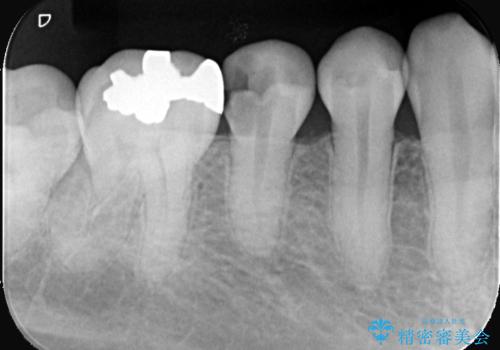

- 虫歯が大きく歯が欠けている状態でした。 そこに食べ物も詰まっている状態でした。

虫歯を除去後、精密根管治療を行い、オールセラミッククラウンで治療を行いました。

虫歯が大きく神経まで到達していました。将来根尖性歯周炎にならないよう徹底的に神経をとり洗浄したうえで被せ物をしています。